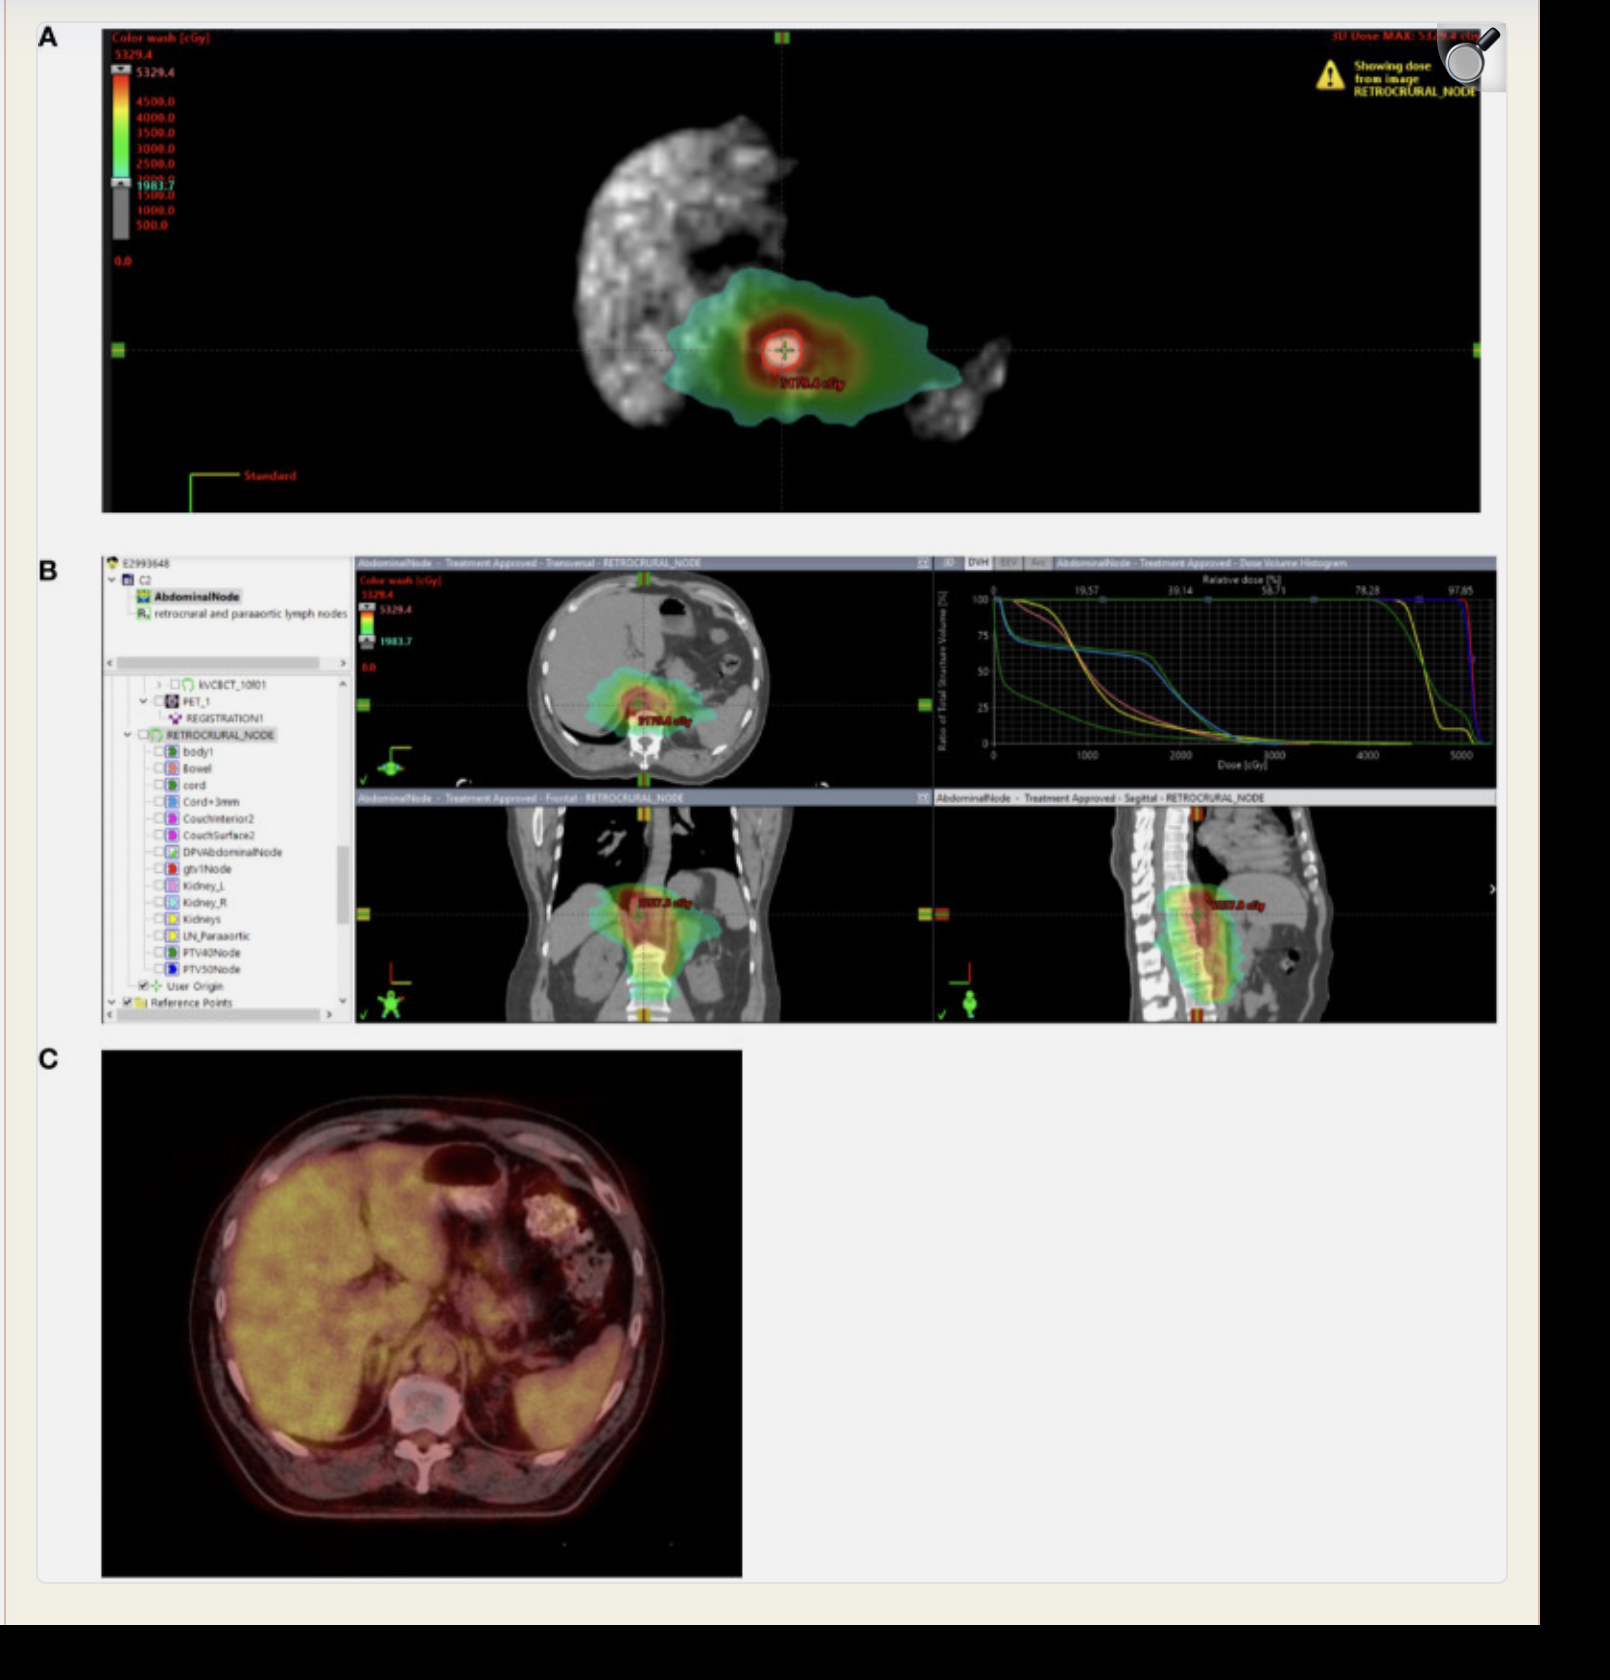

A Radiation dose distribution in a patient treated with lumpectomy with oncoplastic reconstruction

B Bilateral breast MRI with contrast demonstrating subareolar enhancing mass

(A) Radiation dose distribution in a patient treated with lumpectomy with oncoplastic reconstruction. The tumor bed is contoured in red, the PTV30 in cyan, and the PTV28.5 in dark blue. (B) Bilateral breast MRI with contrast demonstrates subareolar enhancing mass to assist with target delineation despite oncoplastic reconstruction.